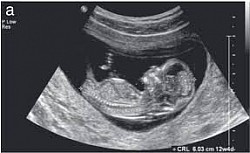

Obstetric ultrasound provides pictures of an embryo or fetus within a woman's uterus, as well as the mother's uterus and ovaries.

> establish the presence of a living embryo/fetus

> estimate the age of the pregnancy

> diagnose congenital abnormalities of the fetus

> evaluate the position of the fetus

3-D ultrasound is to image the fetus and determine if it is developing normally.